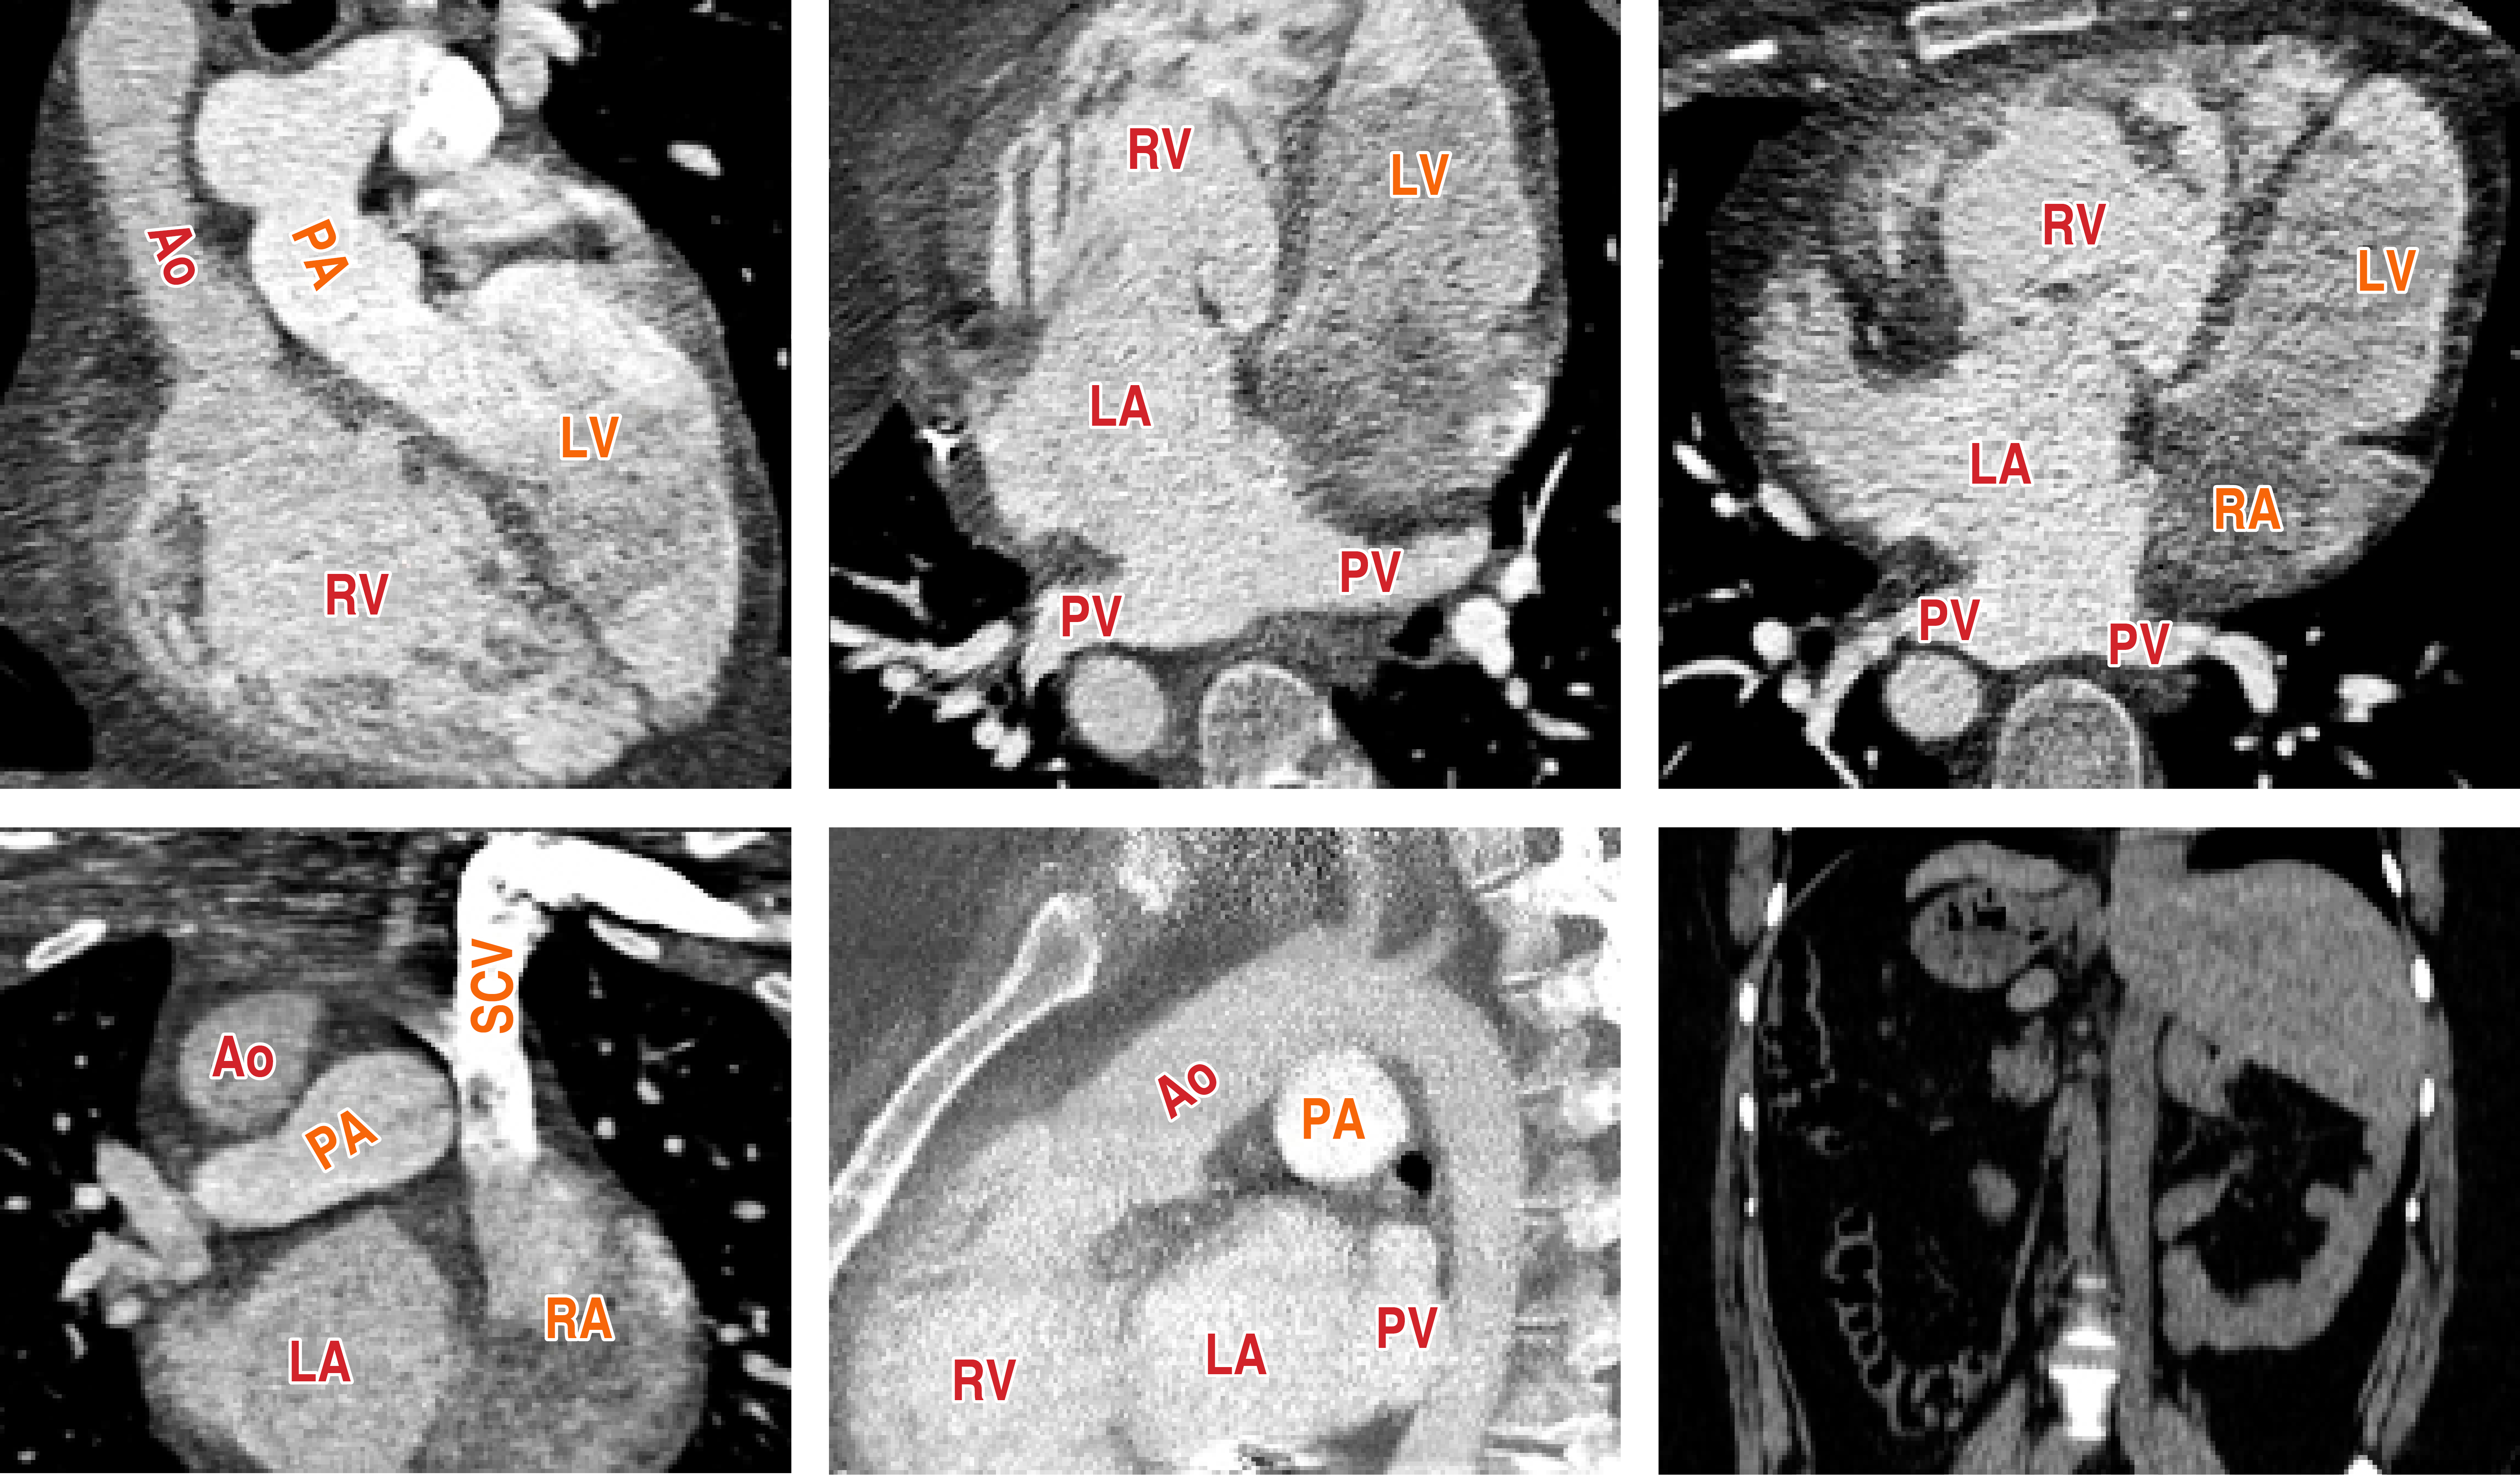

Bloqueo auriculoventricular completo en un paciente adulto con transposición congénitamente corregida de grandes arterias aisladas y situs inversus

La transposición congénitamente corregida de grandes arterias (TccGA) es una cardiopatía congénita poco común. Muchos pacientes permanecen asintomáticos cuando no hay lesiones cardiacas presentes (TccGA aislada). En la TccGA, el sistema de conducción auriculoventricular puede ser anormal, lo que resulta en una disfunción progresiva y, finalmente, en un bloqueo auriculoventricular (BAV) completo. En la TccGA con situs inversus, la vía de conducción se asemeja a un tracto normal, pero el nódulo auriculoventricular se ubica posteriormente. En comparación con el situs solitus, el BAV completo espontáneo es poco común en pacientes con TccGA con situs inversus. Se presenta el caso de una mujer de 40 años sin enfermedades previas ni con antecedentes familiares o personales de cardiopatías que presentó pérdida de conciencia. Al ingreso, el electrocardiograma reveló bradicardia, BAV completo e hipertrofia del ventrículo derecho. Estudios de imagen cardiaca detectaron una TccGA aislada con situs inversus y levocardia. El monitoreo Holter reveló BAV completo intermitente. Las pruebas de esfuerzo demostraron incompetencia cronotrópica. Se le implantó un marcapasos epicárdico y la paciente fue dada de alta asintomática. Tras dos años de seguimiento permaneció asintomática. Este caso ilustra la importancia de imagen cardiovascular para definir la anatomía cardiaca, descartar otras cardiopatías congénitas y facilitar la terapia de estimulación cardiaca en cardiopatías congénitas complejas. Los pacientes con cardiopatías congénitas deben ser tratados por un equipo multidisciplinario con experiencia en estimulación cardiaca permanente.

Figura 2